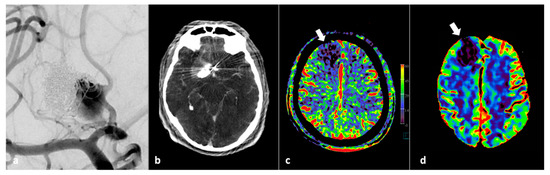

- O’Connor, K.P.; Milton, C.K.; Strickland, A.; Apple, B.; Bohnstedt, B.N. Flat-Detector CT to Quantify Response to Intra-Arterial Spasmolytic Therapy for Cerebral Vasospasm. J. Neuroimaging 2020, 30, 227–232. [Google Scholar] [CrossRef]